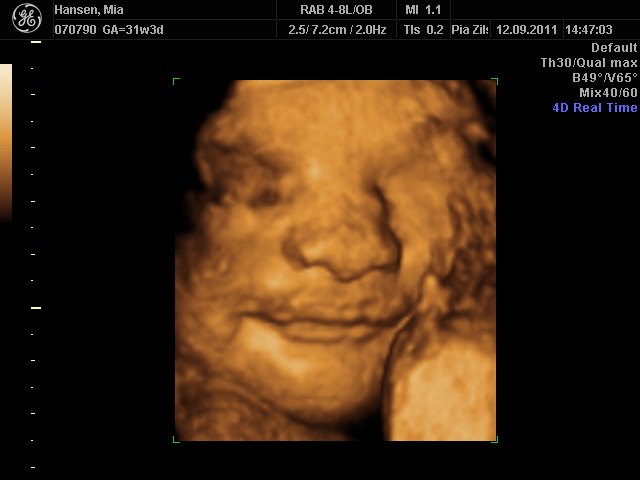

Hun er stadigvæk en rigtig putterøv, men vi fik en masse smil og trut-munde af hende

hun har lange øjenvipper og hår i nakken